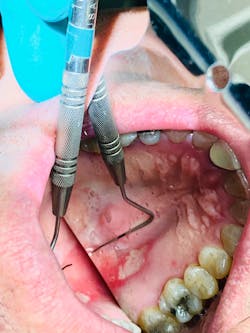

The clinical exam revealed a large 12x9 mm lesion on the left side near the junction of the hard and soft palate. It was creamy white in color with irregular erythematous borders, most notably advanced in the oropharyngeal direction (figure 3).

Differentials include trauma, aphthous major, autoimmune disorders, and viral and nutritional deficiencies.

Furthermore, correlation has been found with the menstrual cycle, periods of stress and anxiety, and family history.1 In this particular case, the patient reported being under severe stress of late due to recent COVID-19 pandemic concerns with work and outside influences.